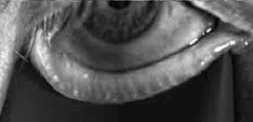

Stades d'atrophie des glandes de Meibomius

Stade 1

Moins de 33% des glandes atrophiées

–Peu ou pas de dilatations

Stade 2

Entre 33% et 66% des glandes atrophiées

– Dilatation et bouchons présents

Stade 3

Plus de 66% des glandes atrophiées

Images meibomiennes de haute qualité

Grâce à une technologie exclusive de traitement des images, MeiboVue® fournit des images de très haute qualité des glandes de Meibomius afin de permettre une évaluation

des structures meibomiennes dans les meilleures conditions.